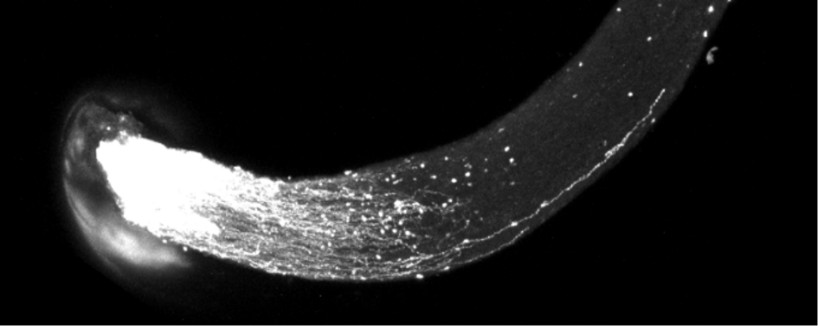

小鼠视神经在给药后,断裂的神经轴突重新长出并不断延伸(图片来源:菁童生命)

JTL-1201a | 视神经修复与轴突再生:针对青光眼及视神经损伤,采用 AAV 递送IPR 因子基因。在目前尚无可恢复受损视网膜神经节细胞(RGC)药物的市场背景下,该方案旨在通过一次性给药实现高效的神经修复与功能重建 。